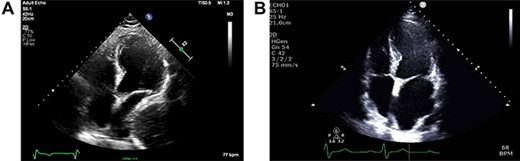

As part of the assessment, computed tomography (CT) coronary angiogram study was performed and it demonstrated a large fluid-filled oesophagus causing partial compression of the left atrium. Barium swallow (Fig. 1A and B), CT chest and abdomen (Fig. 2A and B) and transthoracic echocardiography (TTE) showed a 7.1-cm dilated oesophagus causing left atrial compression and a small hiatal hernia (Fig. 3).

(A) ECHO showing left atrial compression from megaoesophagus during diastole; (B) ECHO showing normal-sized left atrium 3 months after band removal.

Three months after band removal, the patient reported complete resolution of his symptoms. Repeat gastroscopy demonstrated oesophageal mucosal healing and no residual hiatal hernia. TTE showed that left atrium was moderately enlarged (but to a lesser extent compared to previous study) and normal left and right ventricular systolic function and dimensions with estimated left ventricular ejection fraction of 60%. Furthermore, the post-operative Barium swallow study (Fig. 4) demonstrated a 6.7-cm oesophageal dilatation and dysmotility. There was no significant delay in passage of barium into a non-distended stomach. Since band removal his weight had increased by 17 kg (112.8 kg, BMI: 36.4). Further discussions with the patient led to laparoscopic sleeve gastrectomy a month later (Fig. 5).